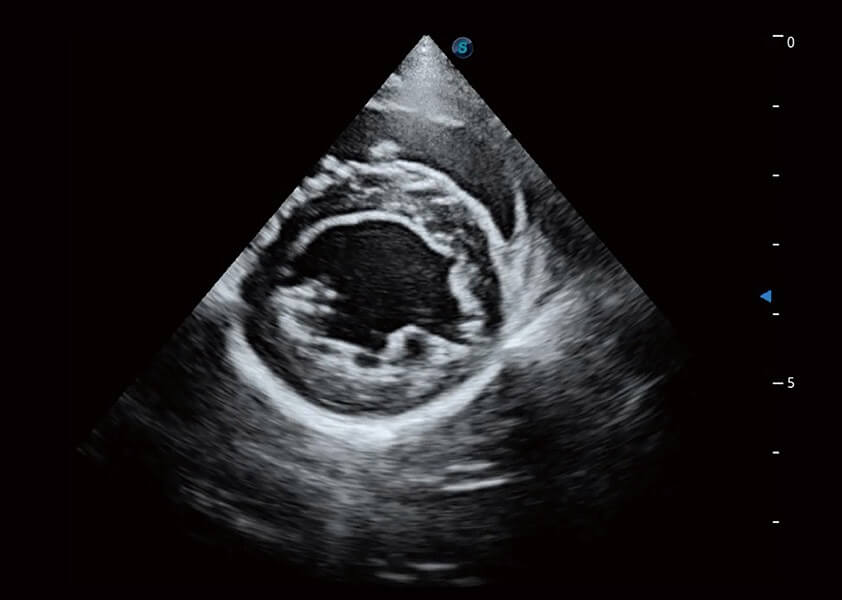

ProPet 60 作为一款高端台式动物超声设备,为动物医生的日常诊断提供了一系列贴合动物临床需求、解决临床实际问题的高级成像功能。凭借全系列高清探头,满足医生对腹部、心脏、生殖、浅表、肌骨等成像的所有需求,切实帮助您提升检查效率,提高诊断信心。

动物是人类最亲密的朋友和最值得信赖的伙伴。16877太阳集团也一直致力于探索动物专用的超声影像解决方案。 全新推出的ProPet系列,是16877太阳集团在动物超声影像智能化、专业化、精准化的一次跨越式革新。动物不能用言语来表述自己的不适,通过超声影像,ProPet系列搭建了动物医生与不同物种沟通的“桥梁”,为动物医生注入了“治愈之力”。